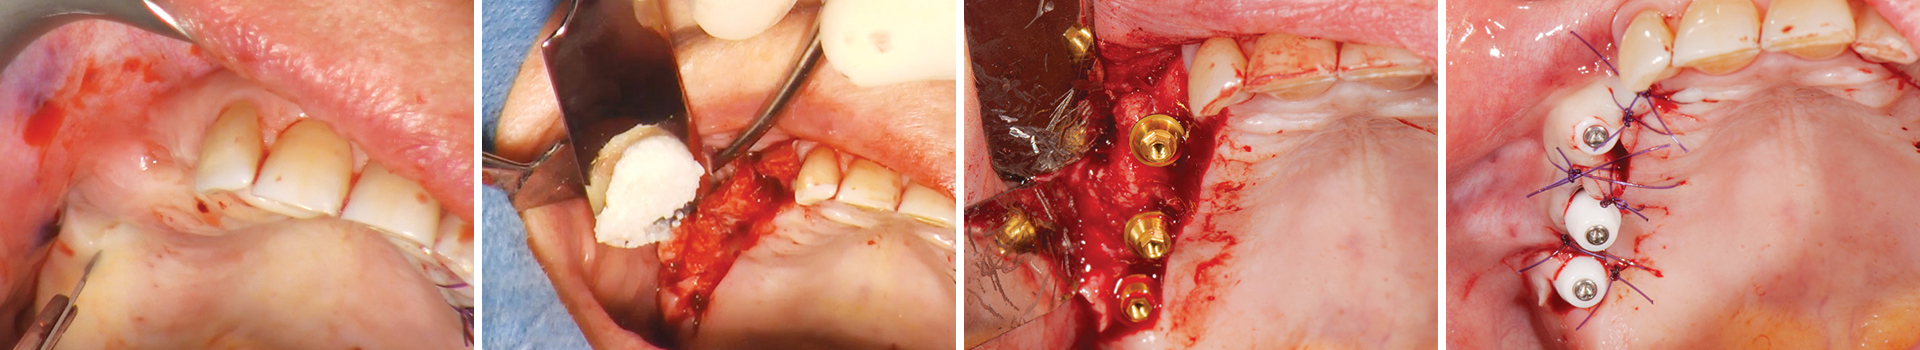

Abbildung 1

Die Versorgung dieses hochatrophen Oberkiefers erfordert einen Sinuslift.

Abbildung 2

Osteotomie und Elevation der Schneiderschen Membran.

Abbildung 3

Augmentation des Sinusbodens mit OsteoBiol® GTO®.

Abbildung 4

Der Augmentationsbereich ist bereit für die Sofortimplantation.

Abbildung 5

Das OsteoBiol® GTO® im Sinus und rund um die Implantate wird kompaktiert.

Abbildung 6

Der augmentierte Sinus.